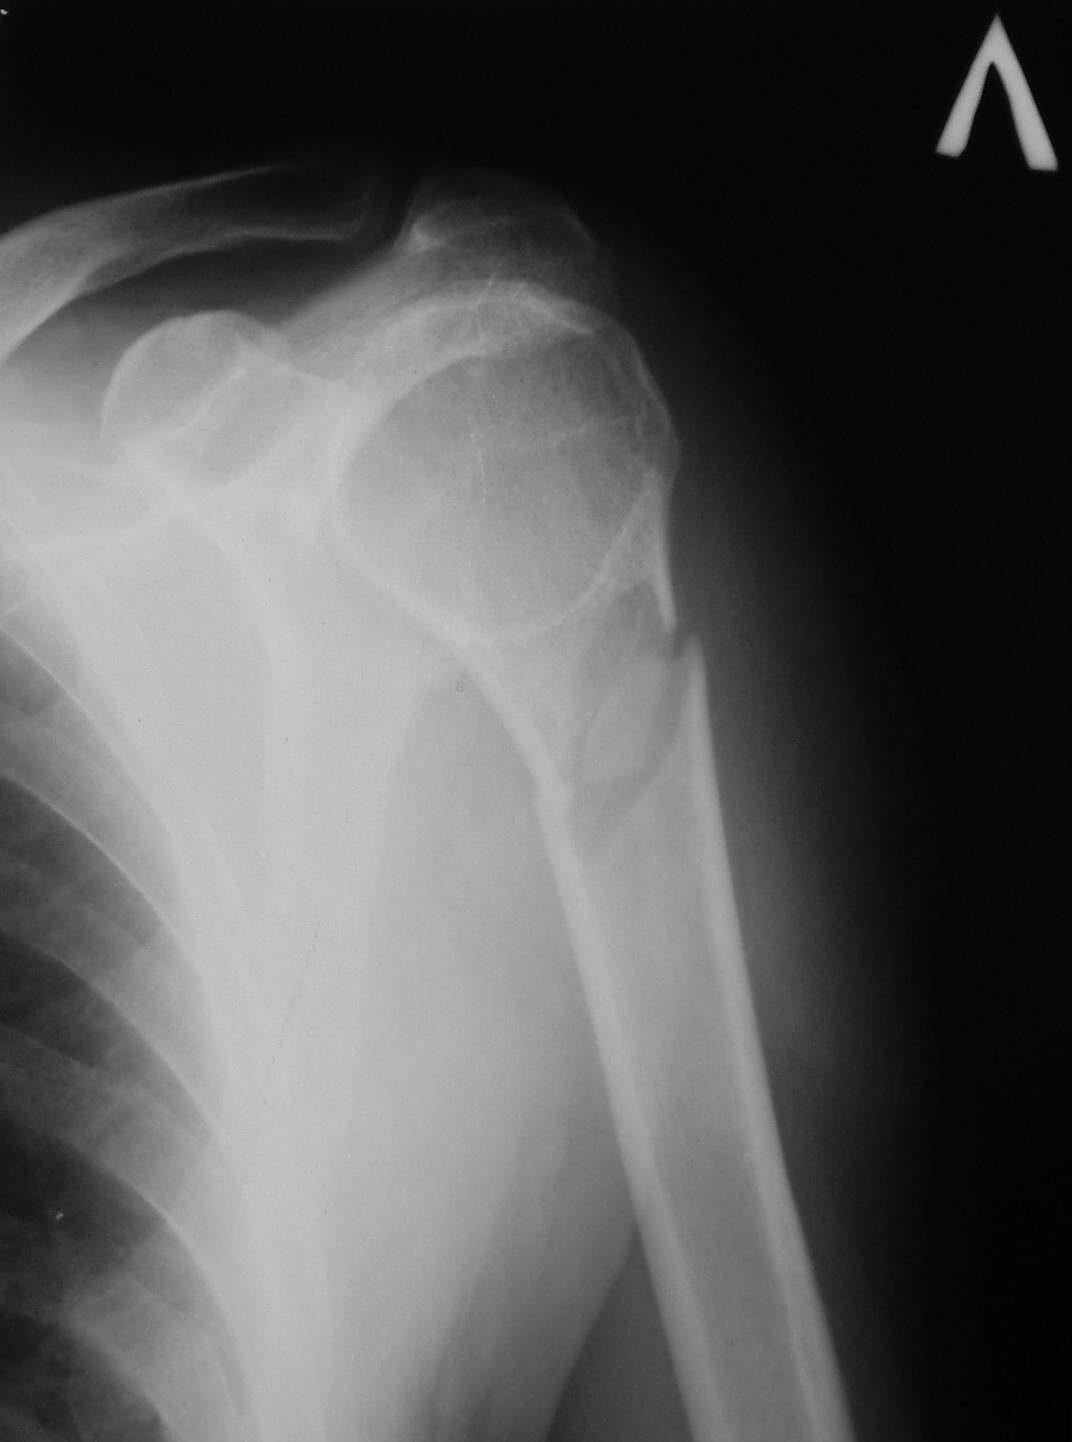

Рентгенологически патологический перелом шейки левой плечевой кости,

Обычный перелом с адекватным механизмом.

наличие секвестра,

Где Вы видите секвестр и что под этим термином подразумеваете? Может быть Вы имеете ввиду небольшой (2х1,5 см) отломок?

шаровидная полость в головке.

Это не шаровидная полость, а нормальное рентгеновское изображение ротированного проксимального отломка

похоже что это киста. а в месте перелома наверное все-таки отломок, а не "секвестр". я думаю КТ поможет в диф. дигностике.

По-моему это киста, похоже на энхондрому. Для уточнения диагноза достаточно обычного КТ.

Что касается секвестра, тут я не согласен. Если приглядеться, то это проэкционный феномен.

Это не полость и не секвестр. Остеопороз головки плечевой кости и фрагмент.С противоположной стороны (другая проекция)также зона остеопороза в области большого бугорка.

Дифференциальную диагностику надо проводить между однокамерной костной и аневризмальной кистой, но расположение в полости кисты тонкого,

линейного фрагмента кости, подтверждает диагноз однокамерной костной кисты.

"Упавший" фрагмент - патогномоническая подсказка к патологическому перелому, часть стенки падает в полость кисты и опускается вниз из-за

силы тяжести.

Подозрение о "шаровидной полости" в головке - это из-за укладки, и на представленном снимке подтверждение правильности рекомендации коллег.